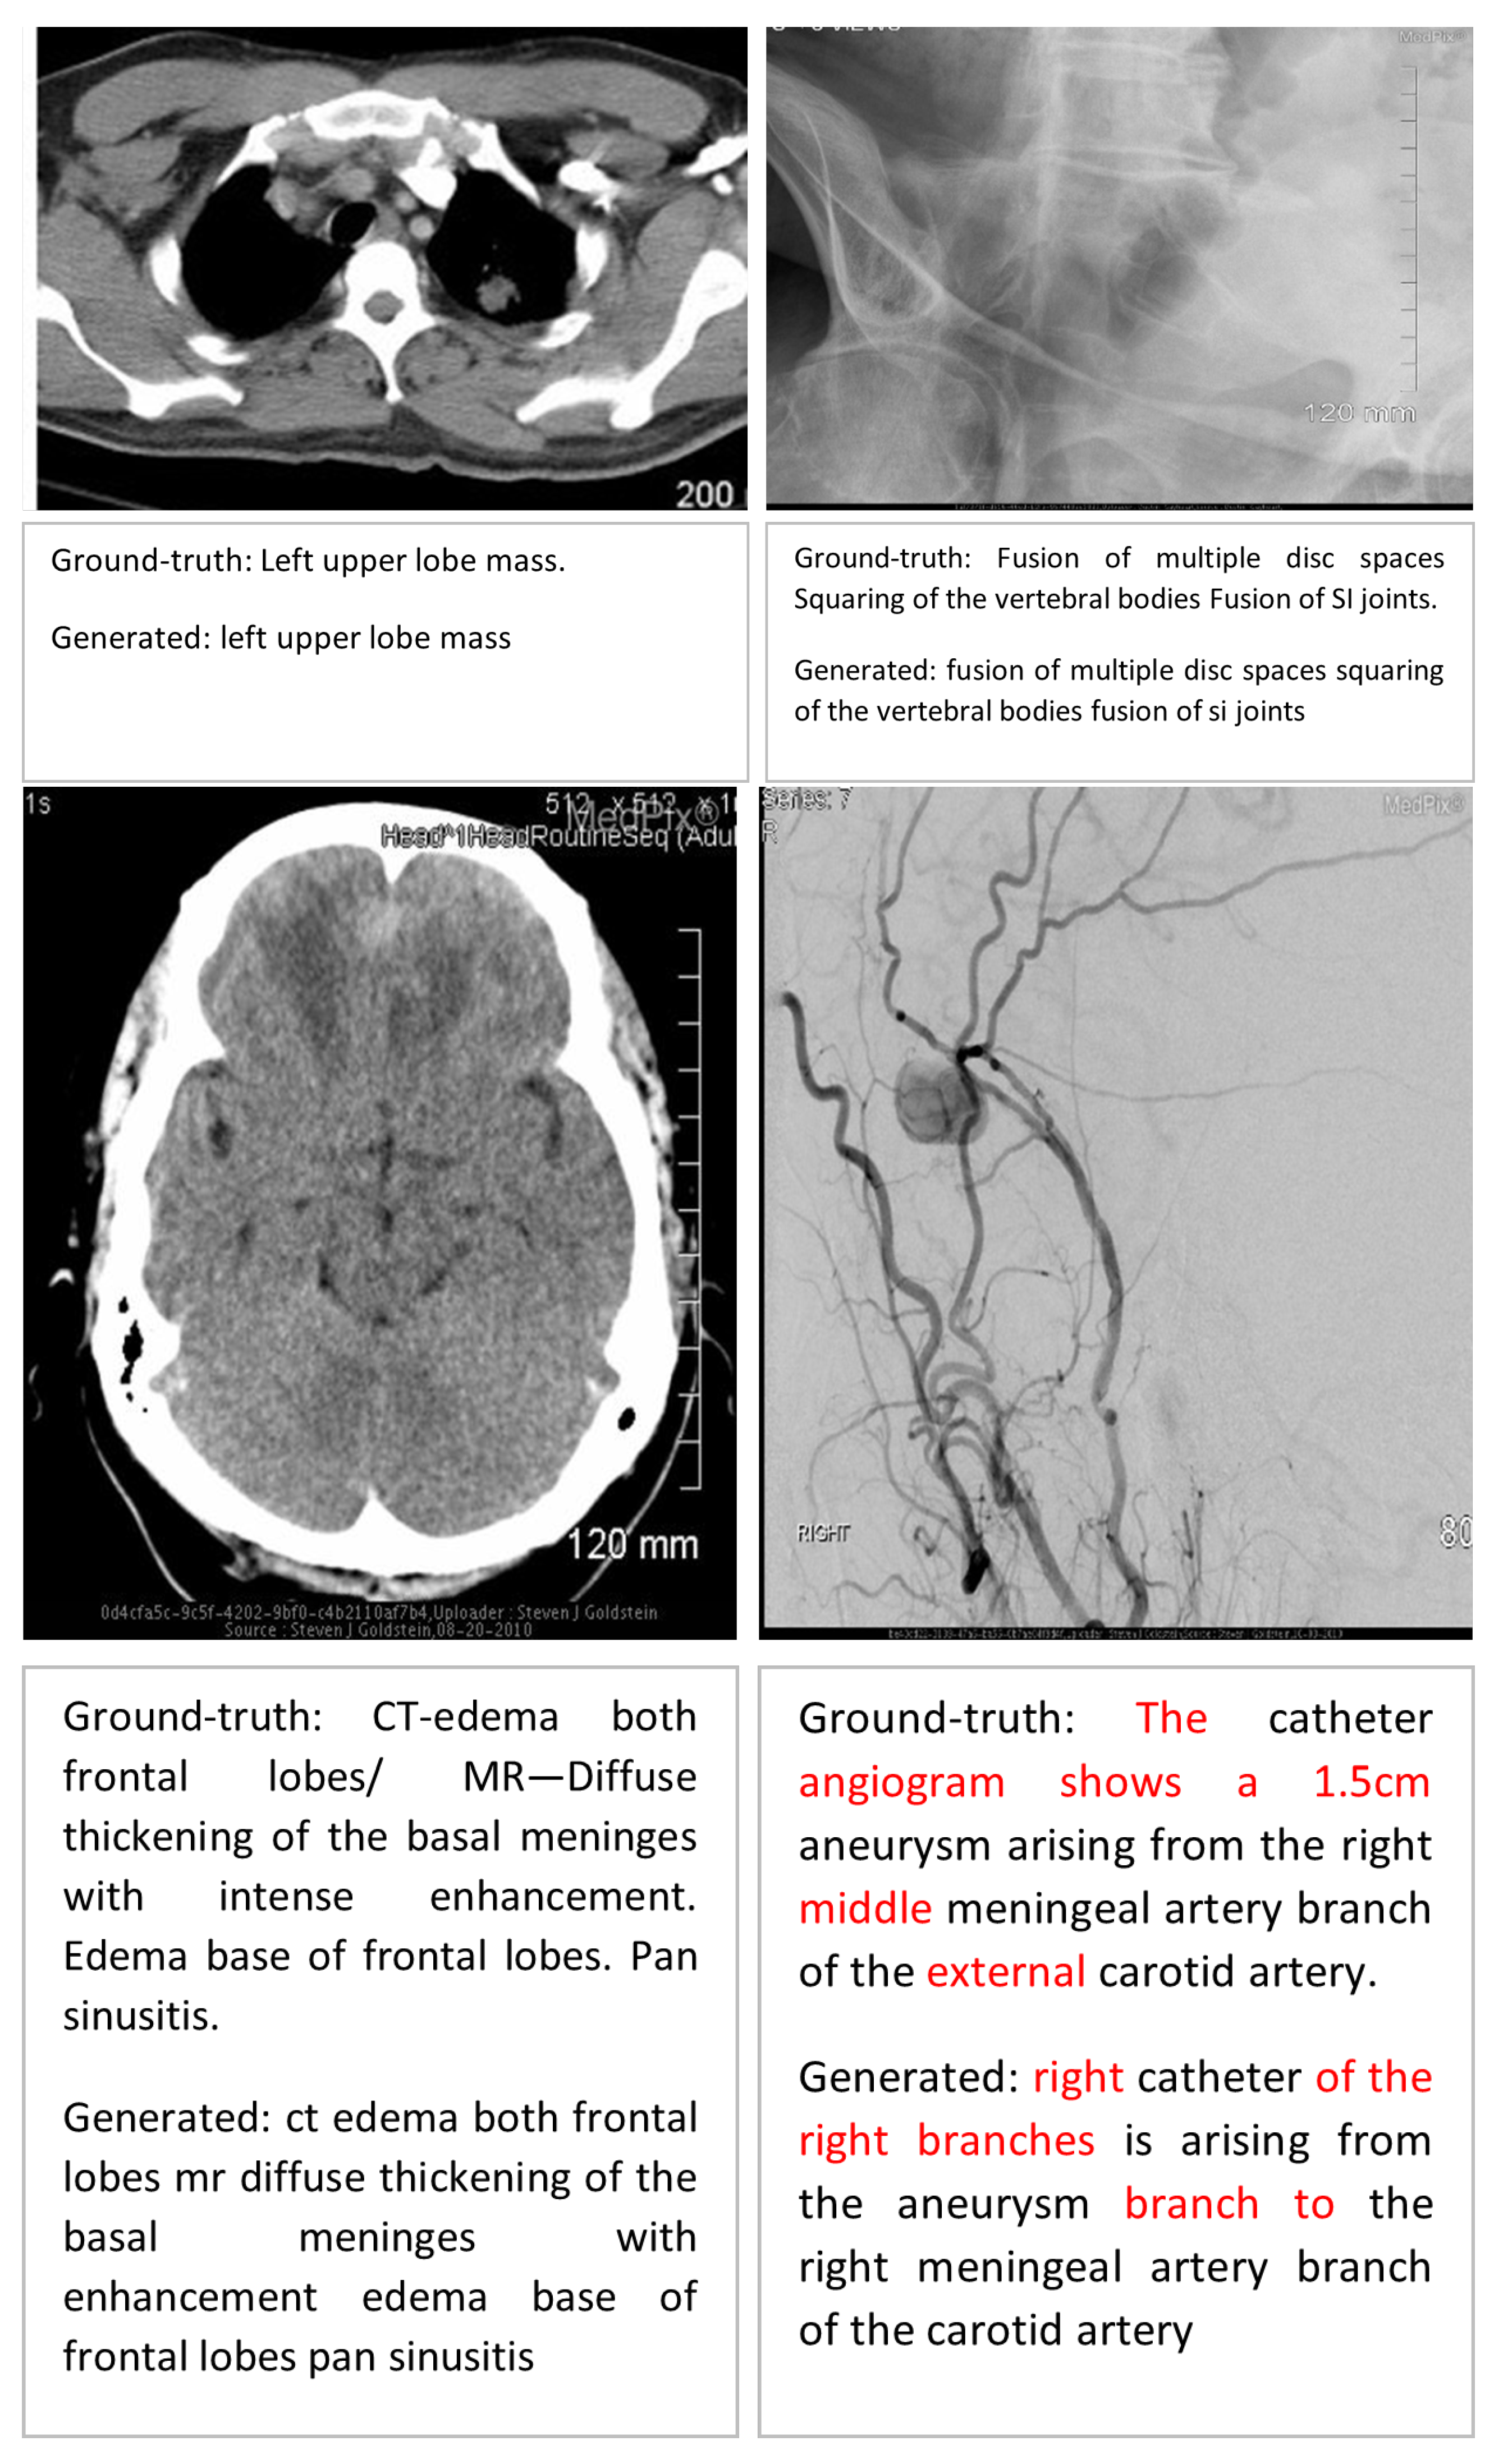

Error Analysis